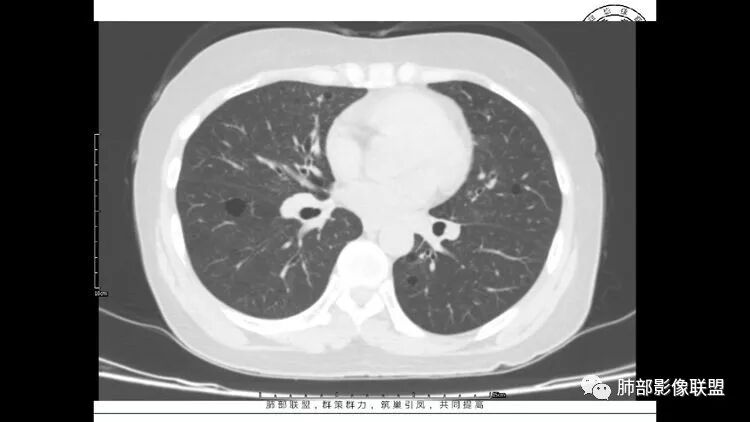

老年女性,眼炎入院,血常规正常,双肺多发囊状影,病变随机分布,形态单一,与血管关系密切,考虑LIP。左下肺混合GGO,边界尚清,贴近囊腔,鉴别腺癌。炎症指标无异常暂不考虑感染性病变。

胸CT:1.双肺多发囊性变,以中下肺为主,病变边缘可见肺动脉,部分囊内可见分隔及肺动脉,双下部分肺野周围可见小叶中心结节及树丫征。

2 左肺上叶尖后段 右肺上叶前段 右肺下叶外基底段 结节影,边界清楚,可见柔软毛刺,左肺下叶后基底段混合密度影。

3.纵隔淋巴结肿大?,以主动脉弓为界向上向下增大。

考虑:淋巴瘤肺浸润,眼部症状考虑与此有关;LIP?;继续鉴别肺腺癌?血管炎?。